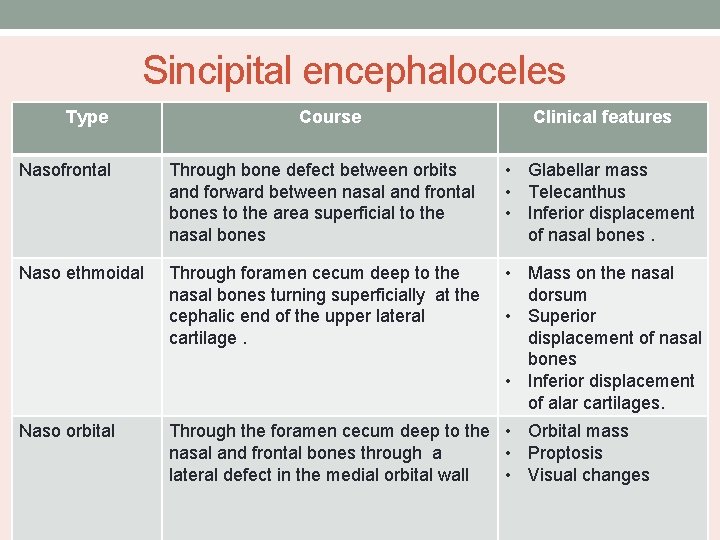

Sincipital encephaloceles Type Course Clinical features Nasofrontal Through bone defect between orbits and forward between nasal and frontal bones to the area superficial to the nasal bones • Glabellar mass • Telecanthus • Inferior displacement of nasal bones. Naso ethmoidal Through foramen cecum deep to the nasal bones turning superficially at the cephalic end of the upper lateral cartilage. • Mass on the nasal dorsum • Superior displacement of nasal bones • Inferior displacement of alar cartilages. Naso orbital Through the foramen cecum deep to the • Orbital mass nasal and frontal bones through a • Proptosis lateral defect in the medial orbital wall • Visual changes